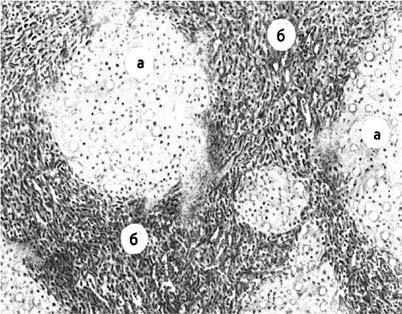

При микроскопическом исследовании дольчатое строение паренхимы печени с характерным расположением венозных сосудов, артериол и желчных капилляров, искажено. Вместо печеночных долек определяются узлы‑регенераты, состоящие из округлых, беспорядочно лежащих клеток разного размера. Портальные синусы и центральная вена отсутствуют или резко деформированы. Узлы окружены широкими прослойками соединительной ткани с редкими венозными, артериальными сосудами и желчными потоками (рис. 78).

Рис. 78. Микроскопическая картина цирроза печени: А – узлы‑регенераты; Б – широкие соединительнотканные перемычки